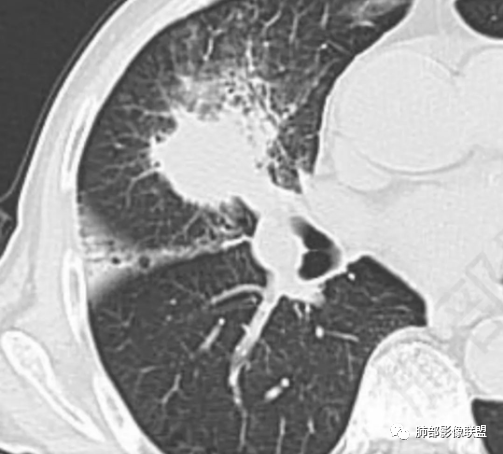

内部大片坏死区,其中还有不规则空洞

坏死腔内壁清,有强化环

肺动脉在实变区走形自然,坏死腔周围受压推移,走形自然,坏死区内破坏

这类坏死区内空洞,提示坏死液比较粘稠

不是液化坏死,液化坏死,这么大,有气体进来按理会形成液气平面

凝固性坏死

炎性标志物升高,有悬浮气泡,是耍首先考虑放线菌